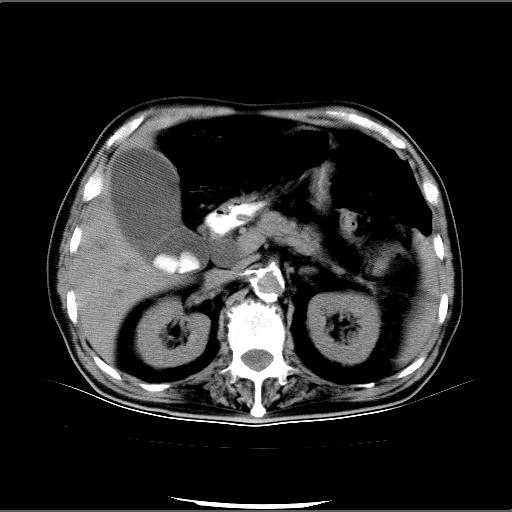

患者男82岁,黄染,发热10天,无腹痛。

1胆总管下端结石伴肝内外胆管扩张;2胆囊颈部结石伴胆囊积液

胆囊多发结石,胆囊积液;胆总管中下段结石,中上段扩张。

胆总管下段结石伴胆道系统扩张;胆囊炎伴胆囊结石.

有时胆总管下段结石的密度并不是均匀的高密度,而是以高密度为主的伴中心等密度的混合物,这与胆道结石的多样性有关,少数时候诊断困难时应结合临床病史,症状等,还有增强扫描都可以帮助明确诊断!!常与胆道蛔虫伴钙化鉴别!

1、胆总管壶腹部结石并胆总管、胆囊及肝内胆管扩张。2、胆囊多发结石。3、两下胸膜局限性增厚。4、胃体部大弯侧胃壁稍厚,建议:多量饮水后增强ct扫描除外占位性病变。

此病例有结果了:患者术后为:胆总管下段结石伴胆道系统扩张;胆囊炎伴胆囊结石。

各位战友分析的都很正确,是一个典型的病例。